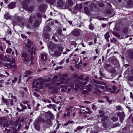

To deal with some of the aforementioned issues, we introduce a new approach for simultaneous H&E stain normalization and augmentation based on the multimarginal Wasserstein barycenter approach. Specifically, the novelty of the paper lies in first introducing the traditional Wasserstein barycenter approach for stain normalization/augmentation (Figure 1), and then introducing the multimarginal version [1, 9] to overcome the limitations of the traditional approach in this context (Figure 2). Note that the traditional Wasserstein barycenter (1 source and 1 reference), although widely employed in computer vision, to the best of our knowledge has never been used for stain normalization/augmentation and the more general multimarginal Wasserstein barycenter (1 source and multiple references) has hardly ever been used in computer vision or medical imaging communities. For more accurate stain normalization, the multimarginal version allows one to incorporate additional distributions by utilizing one or more intermediate reference images (Figure 2). The resultant interpolations span a broad spectrum of stain variations allowing for simultaneous stain normalization and augmentation.

We used MITOS-ATYPIA’14 challenge dataset for evaluating our stain normalization. The dataset includes same tissue sections scanned by two different scanners (Aperio-A and Hamamatsu-H) with total 424 X20 A-H frame pairs, 300 training and 124 testing. Images from scanner A are normalized and matched against the real corresponding images from H (ground truth). As in StainGAN [14], 10,000 random (256256) patches from 300 training frames were used for training (26 epochs with the regularization parameter , learning rate 0.0002, Adam optimizer with a batch size of 4) and 500 patches from 124 testing data used for evaluation. The visual and quantitative comparisons are shown in Figure 3 and Table 1, respectively. For the traditional case (one reference and source), our results are very similar to Reinhard et al. [12] since they also do color matching in Lab space, but our results improve drastically given two reference images. The references in our case span patches with different amounts of background visible. We also tested with different reference images and we show that we get a tighter bound as long as the references contain different amounts of background visibility; see Figure 4 for the box plots of SSIM for different references.